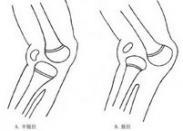

先天性膝关节脱位

628健康网为您分享有关先天性膝关节脱位的症状,先天性膝关节脱位的治疗方法,先天性膝关节脱位的预防知识,先天性膝关节脱...

肘外翻

628健康网为您分享有关肘外翻的症状,肘外翻的治疗方法,肘外翻的预防知识,肘外翻的症状图片,肘外翻吃什么药,肘外翻怎么治...